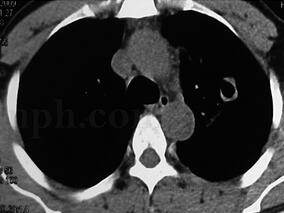

1小时条评论患者,女性,39岁,因咳嗽2年,加重10余天就诊。患者2年前无明显诱因出现刺激性咳嗽,少痰,未重视及就诊,近日咳嗽加重,当地医院查血常规WBC3.0times;109/L,N57.3%,Hb116g/L,PLT110times;109/L,胸片示右下肺占位性病变,我院门诊进一步行肺部CT(图125‐1)...